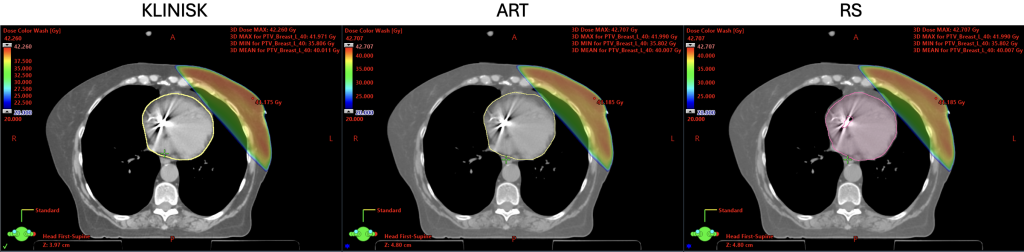

På bildet under ser man et annet eksempel hvor maksdosen er annerledes på grunn av geometriske forskjeller. Her er det vist inntegning av hjerte hvor «KLINISK» er klinisk inntegning og «ART» og «RS» er KI-inntegninger, men bruker ulike segmenteringsmodeller.

En viktig ting å nevne er at selv om KI-modellene tegner de annerledes, så betyr det ikke nødvendigvis at den ene er bedre enn den andre. Dette blir mer et definisjonsspørsmål på hvordan strukturer skal tegnes.